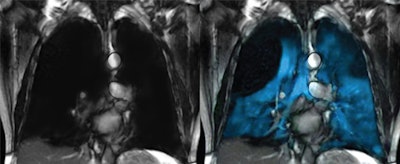

Xenoview is a hyperpolarized xenon (Xe-129) gas contrast agent indicated for use with MRI in evaluating lung ventilation in adults and pediatric patients ages 12 and older. The combination of Xenoview with the 7700 multinuclei scanner may allow clinicians to view a patient's lungs in greater detail, while also enabling measurements of lung ventilation, according to the firms.

The first Xenoview clinical scan in North America using a Philips MR scanner took place at Cincinnati Children's Hospital Medical Center. Philips' multi-nuclei imaging scanning module, which has received U.S. Food and Drug Administration 510(k) clearance, was utilized in the study.